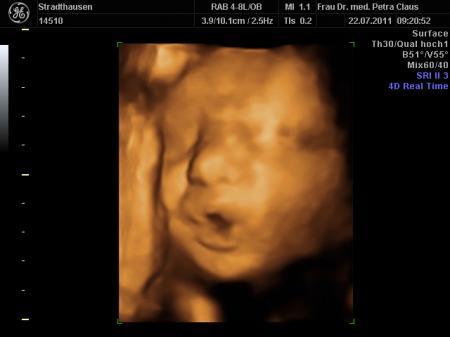

komme grad von der VU und bin ja so ein bisschen megahappy. Endlich hab ich meinen Kleinen wieder im 3D ultralschall gesehen und der war heut vielleicht in Action

...schon beim CTG hat er rumgekaspert, fleißig gegen den Schallkopf getrampelt und sich immer weggedreht, zum Schluss noch nen schönen Schluckauf....voll süß

...alles soweit unauffällig. Dann beim Ultraschall ging es richtig los...Schnute auf, Schnute zu.....wir haben uns köstlich amüsiert. Jedenfalls hat er seinen kleinen Wachstumsrückstand wieder gut aufgeholt, hoffentlich bleibt alles so schön und gesund.

Maße bei 32+4

Gewicht: 2150 gramm

Länge: 42-43 cm....

anbei noch ein paar Bildchen.